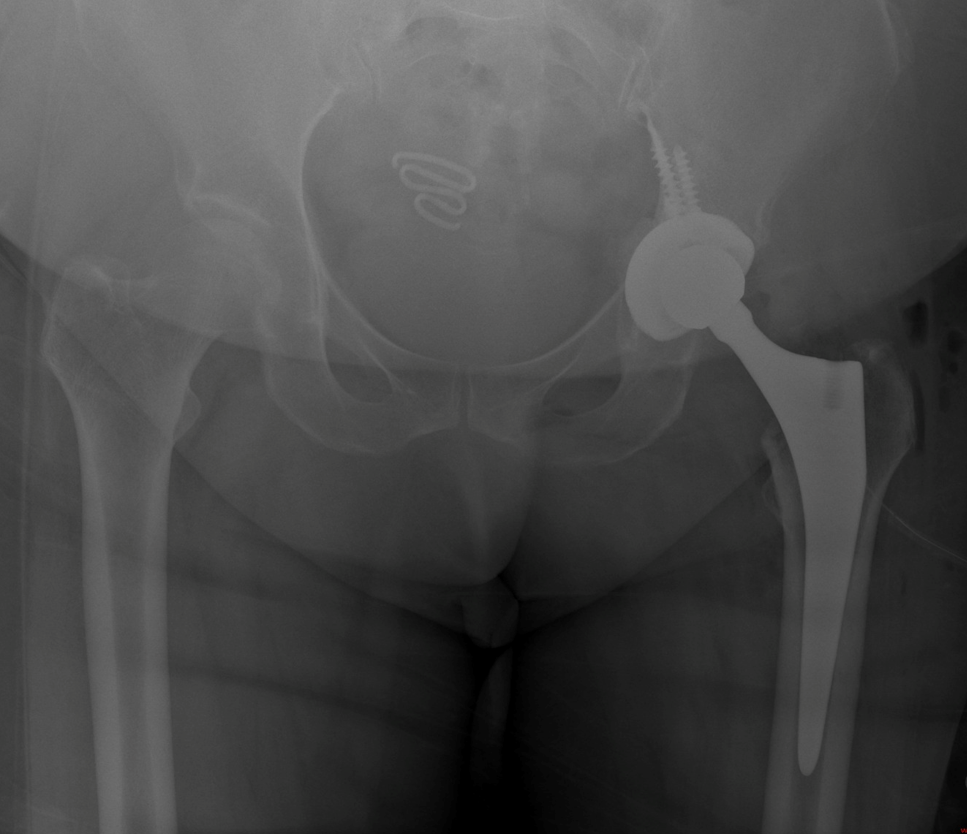

Eklem protez cerrahisi (artroplasti), halk arasında “eklem protezi” olarak bilinir. En çok kireçlenen eklem ve en çok protez uygulanan eklem diz eklemidir. Bunun ardından Kalça eklemi gelir. Ayrıca omuz, ayak bileği ve el bileği eklemlerinde de kireçlenme yani artroz sonrası eklem protez cerrahisi uygulanmaktadır. Eklemlerimiz zamanla yıpranabilir veya kireçlenme nedeniyle görevini yapamaz hale gelebilir. Bunun birçok sebebi vardır. Bu durumda protez cerrahisi sayesinde ağrısız hareket etmek, günlük hayata geri dönmek mümkündür. Türkiye'de protez cerrahisi 90'lı yıllarda İstanbul, İzmir ve Ankara gibi illerde yapılırken şu an her şehirde yapılabilmektedir. Ege Üniversitesi'nde diz protezi ve kalça protezleri konusunda 40 yıllık deneyimi olan Hakkı Sur ile eğitim aldıktan sonra Fransa'da yine ünlü protez merkezinde birçok vakaya katılmış ve yapmış olmanın bu cerrahideki önemini meslek hayatımda daha da idrak ettim.

En sık uygulanan eklem protezleri: